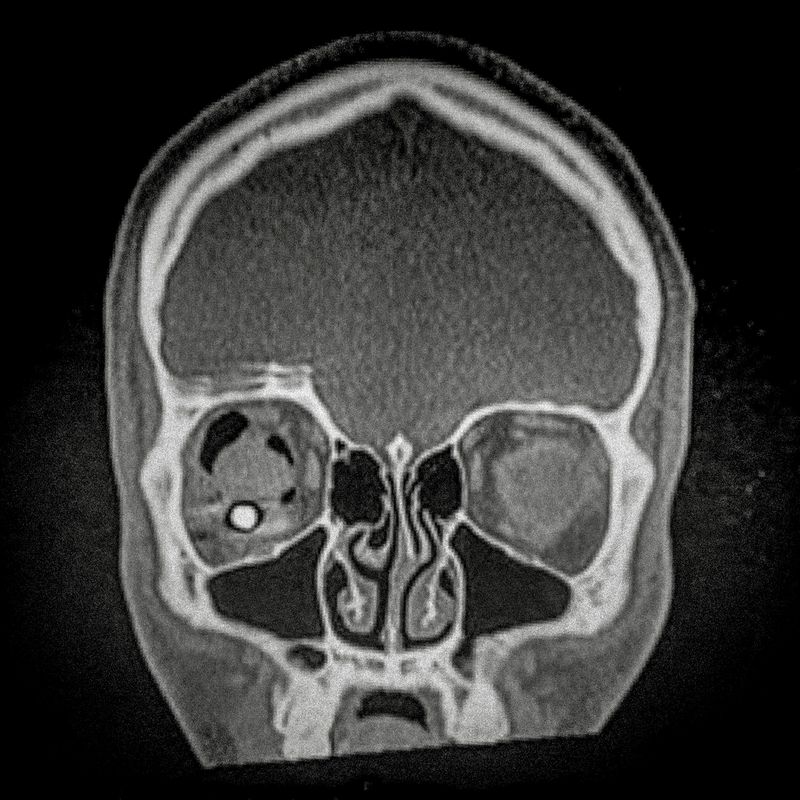

X ray showing the embedded pellet of an injured man during Santiago protests.

© Cristóbal Olivares - X ray showing the embedded pellet of an injured man during Santiago protests.